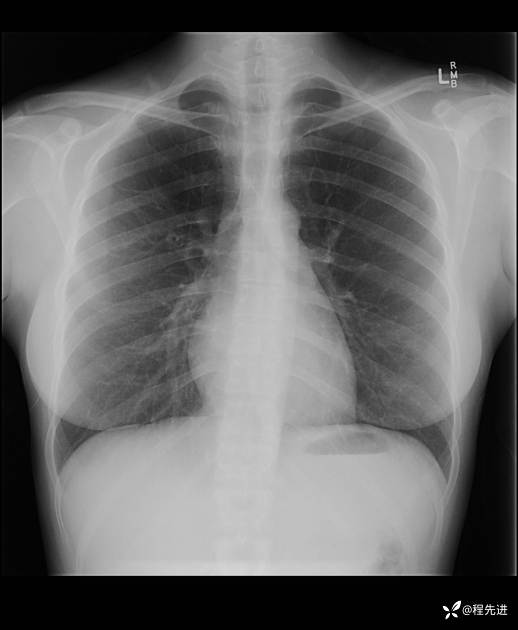

患者性别:女

患者年龄:25岁

简要病史:下胸部疼痛3天

CT增强:

img